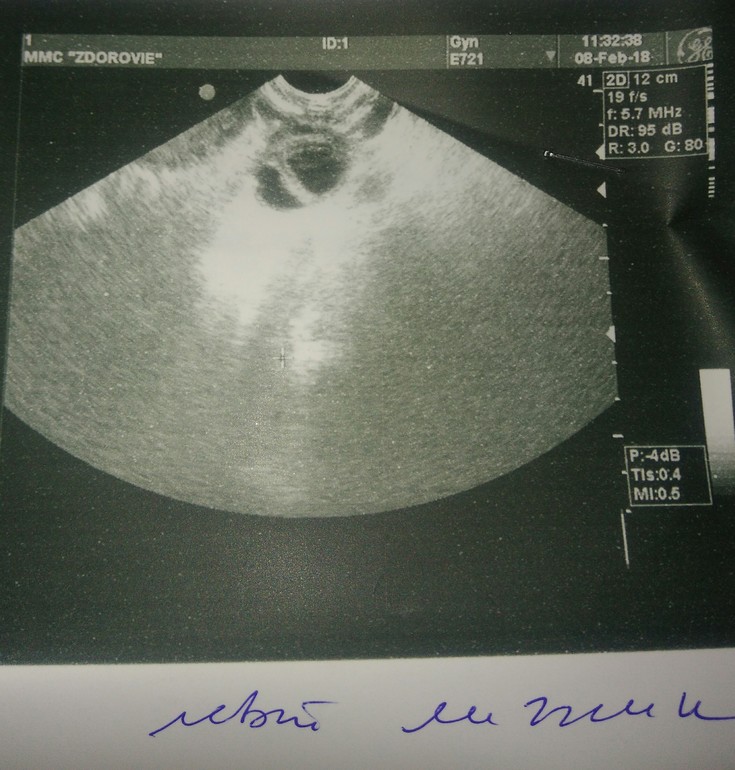

Узи

Девочки, посмотрите пожалуйста фото и описание яичников по УЗИ. На фото левый яичник. Про включения которые там написаны. Кто нибудь знает как выглядит жт на УЗИ( что это 2 жт или жт и киста)? У кого также было? Спасибо)